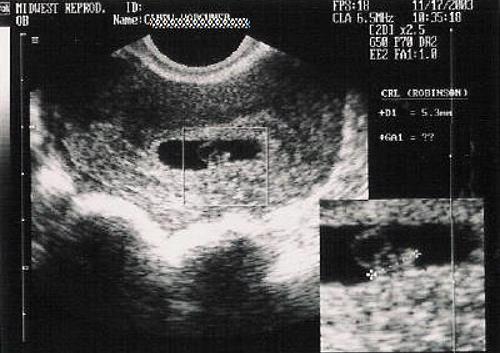

6 тиждень вагітності: узі плода на шостому тижні

У шість тижнів вагітності розміри ембріона наближаються до розмірів горошини. При УЗД в шість тижнів вагітності виміряється тім'яної розмір, це довжина ембріона. З цього розміру з допомогу УЗД можночетко визначити термін вагітності, особливо це важливо, якщо є розбіжності з менструальним терміном вагітності. Продовжує визуализироваться при УЗД в шість тижнів вагітності жовтковий мішок поруч з ембріоном і жовте тіло в яєчнику при. Якщо при УЗД в п'ять тижнів вагітності ще немає достоветних даних про збільшення розмірів матки, то при УЗД в 6 тижнів вагітності матка збільшується в розмірах. У стандартних протоколах УЗД в 6 тижнів вагітності зазвичай не вказуються розміри матки, так як ці вимірювання не мають практичного значення. УЗД в 6 тижнів вагітності дозволяє оцінити наявність развівоющейся вагітності навіть при оглядовому скануванні через живіт, але більш чіткі дані можна отримати саме при трансвагинальном УЗД.

Крім перерахованих вимірювань іданних, при УЗД в 6 недельбеременності вимірюється плодовий мішок. Терміни вагітності більш точно розраховувати не по середньому діаметру плідного мішка, а за розміром ембріон - його куприка-тім'яної розміру (КТР). Обов'язково оцінюється серцева скоротність ембріона. Саме за наявністю серцевої діяльність Ділан висновок при УЗД в шість тижнів вагітності про розвиток вагітності, про її прогресуванні.

Фото УЗД плоду на 6 тижні вагітності